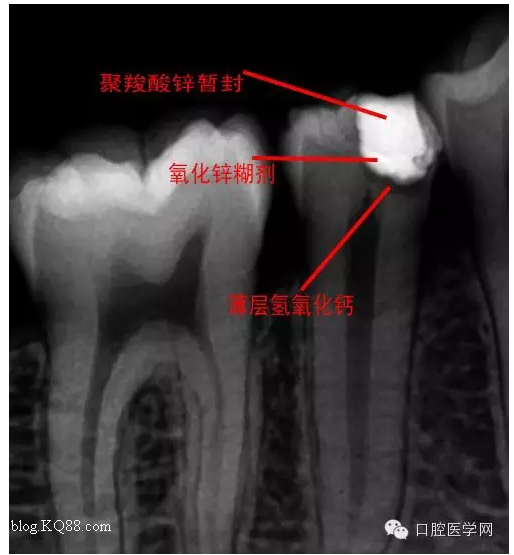

去腐,備洞。發(fā)現(xiàn)已經(jīng)露髓。根據(jù)年輕恒牙保存活髓治療原則。選擇直接蓋髓術(shù)?;颊呤俏业闹种辣4婊钏璧闹匾裕灾皇亲隽撕唵蔚臏贤?。如果其他病人遇到這種情況術(shù)前溝通很重要。首先灌輸保髓的重要性,告知術(shù)后反應(yīng),以避免不必要的麻煩

術(shù)后第二天問小伙:什么反應(yīng)?答:輕微脹痛,無冷熱痛,無咬合痛。我驚愕因為回答的夠?qū)I(yè)。不愧是金牌助手。呵呵,如果病人這樣回答您會???在啰唆幾句:操作中無菌是關(guān)鍵。從露髓的一刻起就不應(yīng)與唾液接觸。去腐后生理鹽水沖洗窩洞,但不要加壓或生理鹽水棉球輕輕擦拭窩洞。柔風(fēng)吹干